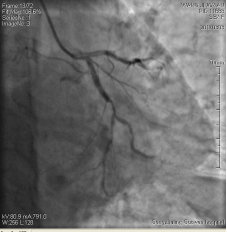

3月3日14時30分:經(jīng)右橈動脈行冠脈造影見:左主干未見明顯異常,TIMI血流3級,前降支開口正常,近中段20%狹窄,TIMI血流3級;回旋支開口正常,中遠(yuǎn)段75%狹窄,TIMI血流3級。右冠狀動脈開口正常,中段長病變,最重99%狹窄, TIMI血流3級。

圖1 回旋支遠(yuǎn)段70%狹窄 圖2右冠脈中段99%狹窄